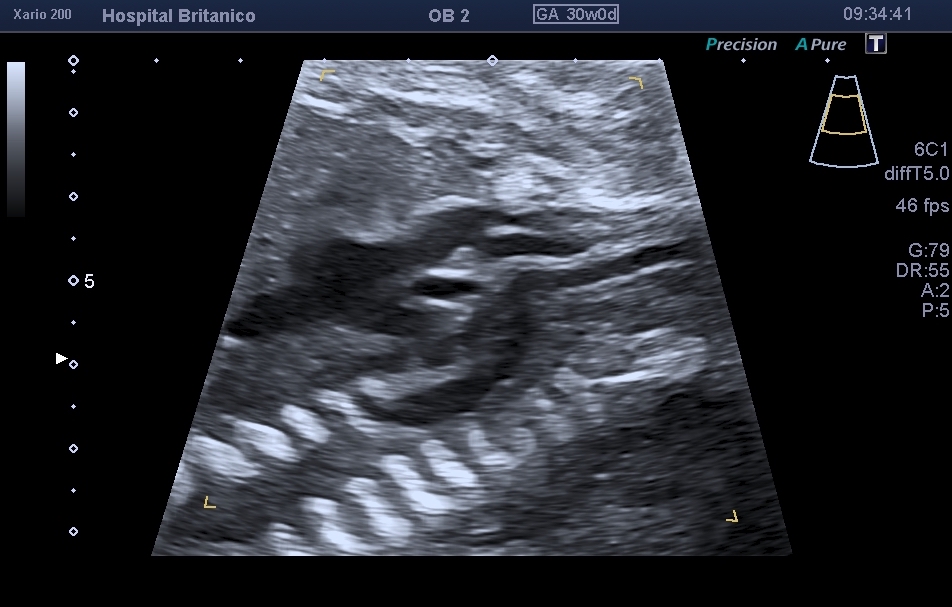

Se presenta a la consulta una paciente secundigesta de 30 años de edad cursando embarazo de 27.4 semanas. Es derivada del interior del país por hallazgos sugestivos de patología cardíaca en el estudio morfológico del segundo trimestre. No presenta antecedentes de relevancia. Adjunta un screening de aneuploidías del primer trimestre con resultado bajo riesgo. Durante la evaluación ultrasonográfica cardíaca, se observaron los siguientes hallazgos: Figuras 1-4. Elija la opción correcta: a. Se observa una comunicación interventricular (CIV) de salida, sin otros hallazgos relevantes. b. Los hallazgos son compatibles con interrupción del arco aórtico de tipo B. c. Los hallazgos son compatibles con coartación aórtica (dominancia de cavidades derechas y alteración en el corte de 3 vasos). d. Los hallazgos son compatibles con tetralogía de Fallot con atresia pulmonar.

El diagnóstico prenatal se basa en la sospecha de esta cardiopatía mediante  la visualización de signos ecográficos indirectos y su confirmación mediante signos directos. Los signos indirectos incluyen la asimetría de cavidades ventriculares en el plano de cuatro cámaras, a expensas de las izquierdas de menor tamaño, similar a lo observado en la coartación de aorta. Esta asimetría se observa también en el tracto de salida del ventrículo izquierdo, en donde se ve menor calibre de la aorta ascendente. Sin embargo, dado que el tipo B es el más frecuente, y en la mayoría de los casos coexiste con una CIV subaórtica, es habitual encontrarse con un plano de 4 cámaras normal (Fig. 1). La CIV, salvo que sea de gran tamaño, no se suele evidenciar en el corte de 4 cámaras, y consecuentemente, solo se evidencia la asimetría a nivel de los grandes vasos (Fig. 2). En el corte de los 3 vasos, es evidente la disminución del calibre de la aorta ascendente que es menor al calibre de la arteria pulmonar, pero más llamativamente, menor al calibre de la vena cava superior, observada en este mismo plano (Fig. 3). En el corte de 3 vasos y tráquea, no es posible evidenciar la continuidad del arco aórtico. Es frecuente observar una disminución del tamaño del timo, y aún su ausencia, dado que esta cardiopatía se encuentra muy asociada a la microdeleción 22q11.2.